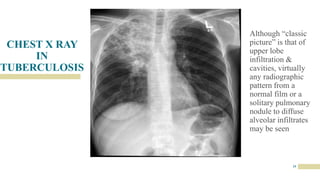

CHEST X RAY

IN

TUBERCULOSIS

19

Although “classic

picture” is that of

upper lobe

infiltration &

cavities, virtually

any radiographic

pattern from a

normal film or a

solitary pulmonary

nodule to diffuse

alveolar infiltrates

may be seen

20